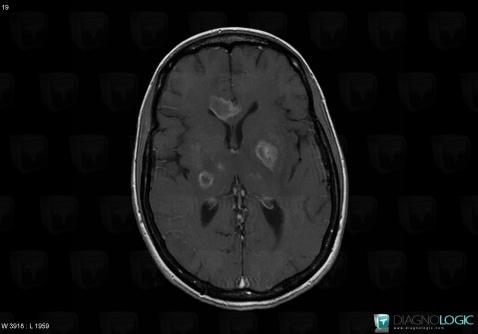

Toxoplasmosis, Cerebral hemispheres, Basal ganglia and capsule, MRI

Here is the specific information in the key image above:

- Diagnosis Toxoplasmosis (link to Abscess), Location(s) Basal ganglia and capsule, with gamuts DWI hyperintense lesionCerebral hemispheres, with gamuts DWI hyperintense lesion